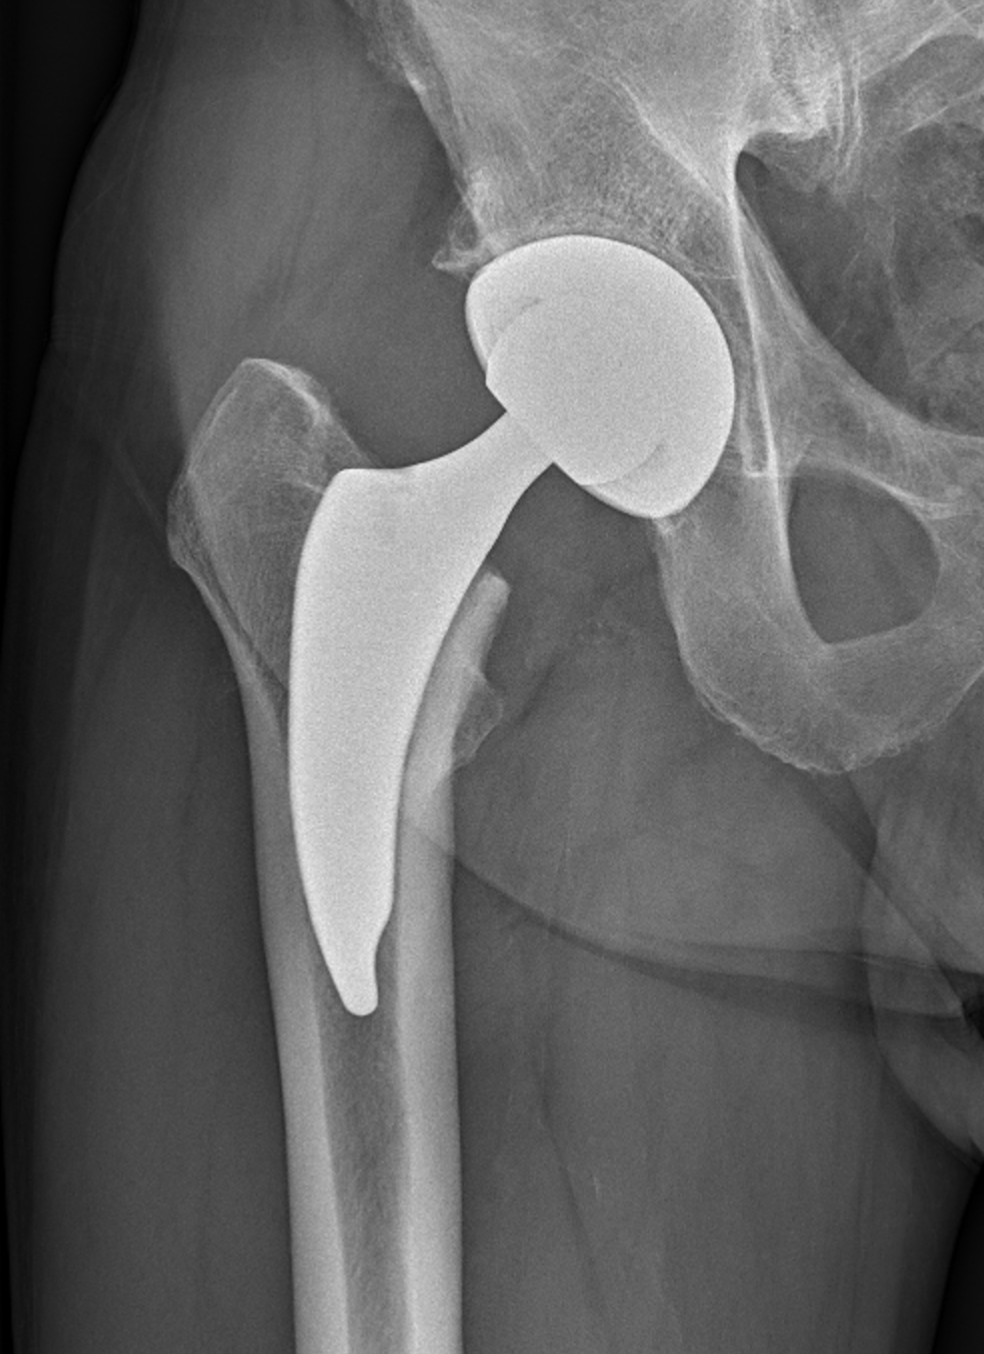

Endoprotéza je umělý kloub, který dokáže nahradit opotřebovaný či poškozený kloub člověka. Nejčastěji jde o kyčelní či kolenní kloub.

Náhrada kloubu je operace, při níž lékaři odstraní poškozené části kloubu a nahradí je speciálním implantátem – endoprotézou. Operace se provádí v celkové či spinální anestezii, případně v kombinaci s regionální svodnou anestezií.

U celkové náhrady (tzv. totální endoprotéza, TEP) jsou umělým kloubem nahrazeny všechny kloubní plochy.